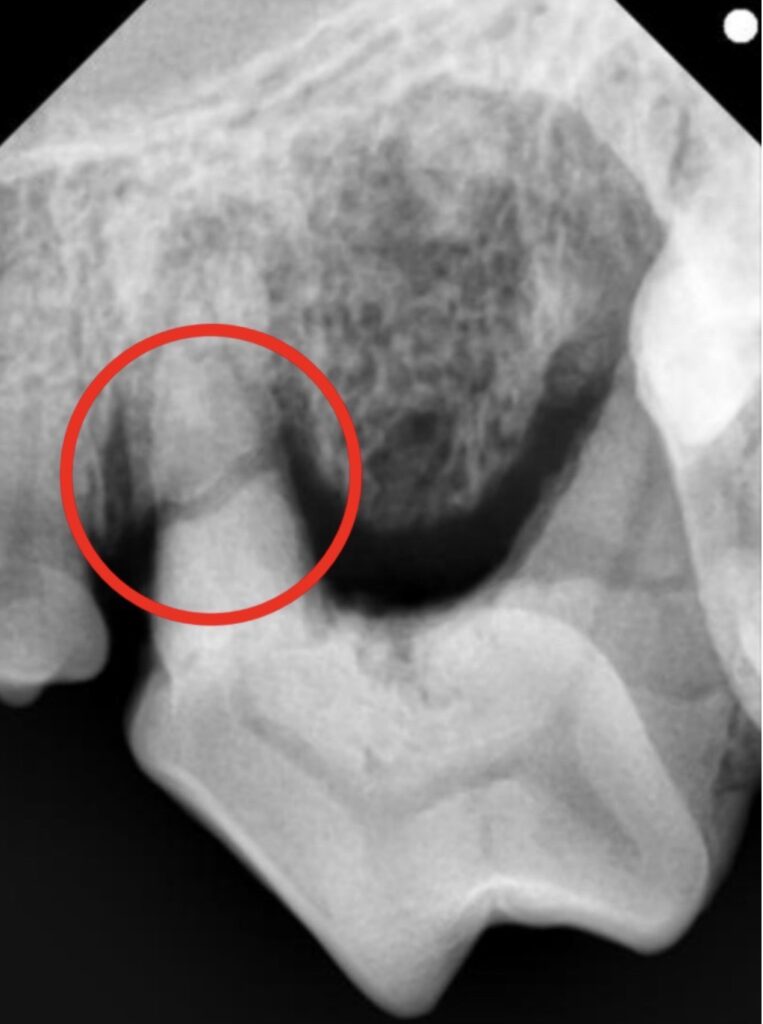

左上顎第4前臼歯では歯根破折、左上顎第2切歯では破折(露髄)が認められました。

破折(露髄)

歯根破折